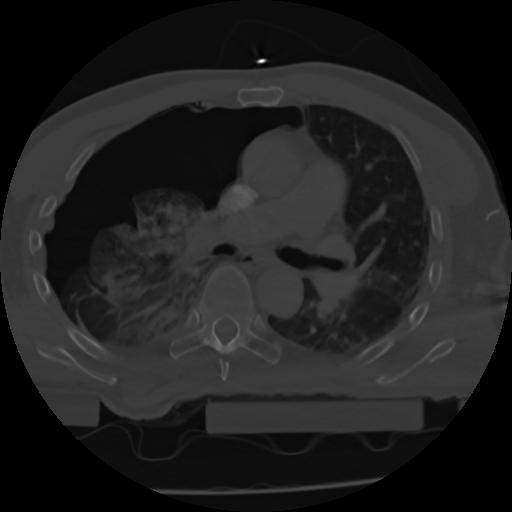

21 ANGIO,CE,Axial,3.0,ANGIO,,